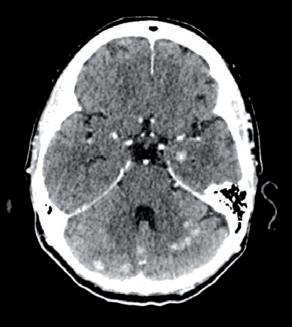

Con la PET/TC eseguita a novembre del 2016 si evidenziava la presenza di significative alterazioni di distribuzione del radiofarmaco a carico del fegato e a livello scheletrico, come da alterazioni di natura sostitutiva. In particolare, in corrispondenza del fegato, si segnalava significativa captazione focale a livello del settimo segmento e altra poco più cranialmente. Si evidenziavano poi plurime significative captazioni estese a tutto il rachide cervicale, dorsale e lombare (SuvMax fino a 18) oltre che a tutto il bacino, oltre che a livello delle coste bilateralmente, clavicola sx, manubrio sternale, entrambe le scapole, entrambe le teste e diafisi prossimali omerali, diafisi omerale destra, entrambi i femori a livello delle teste, delle regioni trocanteriche, maggiormente a sx, diafisi prossimali femorali, corrispettivo alle immagini TC ad alterazioni addensanti, in parte ad alterazioni litiche, in parte a malattia ancora in fase pre-radiologica (figura 1).

1. TC/PET TB, novembre 2016.

Figura

Alla RMN encefalo del 18/02/2022, in sede cerebellare sinistra si conferma la presenza di alterazione sospetta in senso ripetitivo di 15 mm, adesa alla dura madre.

Si evidenzia alterazione osteostrutturale patologica della teca cranica in sede temporo-parietale destra associata a ispessimento lineare della meninge adiacente (figura 3).

TC e RMN encefalo con mdc, febbraio 2022.